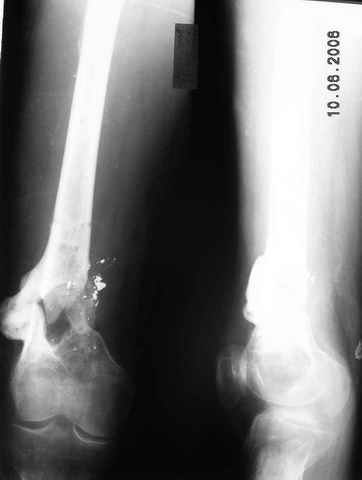

Возможно, проф. Лазарев предложит другой вариант, а в наших условиях мы бы закрыто заштифтовали бы бедро антеградно. Устранили бы варус, используя голень как рычаг, вероятнее всего, даже дистрактор не понадобился бы. В приницпе, можно и ретроградно ири наличии движений в колене, но варус будет труднее устранить - можно и предварительно аппаратом в таком случае.

Стержень можно использовать и обычный потолще, но лучше бы с возможностью введения большего, чем два фронтальных, числа запирающих винтов.